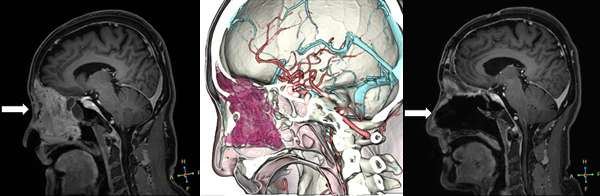

画像技術の発展により、術前に詳細なシミュレーションを行うことが可能となりました。当院では術前にシミュレーションを行う事で、低い侵襲で大きな治療効果が得られるよう術前計画を行っています。

鼻・副鼻腔から頭蓋底に進展する腫瘍です。

耳鼻咽喉科と合同手術を行い、開頭・経鼻手術を同時に行って摘出しました。